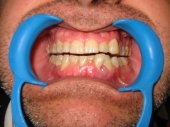

Alteraciones de los tejidos parodontales (encía, ligamento y hueso) por problemas funcionales |

Sangrado gingival espontáneo, infecciones

en las encías o movilidad dentaria debidos al desequilibrio oclusal